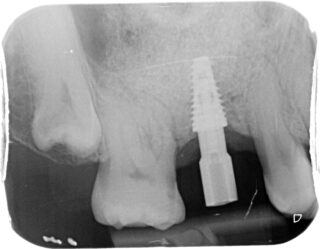

A dental implant, usually made of titanium, is placed into the jawbone. Over time, the implant fuses with the bone to create a solid and stable foundation.